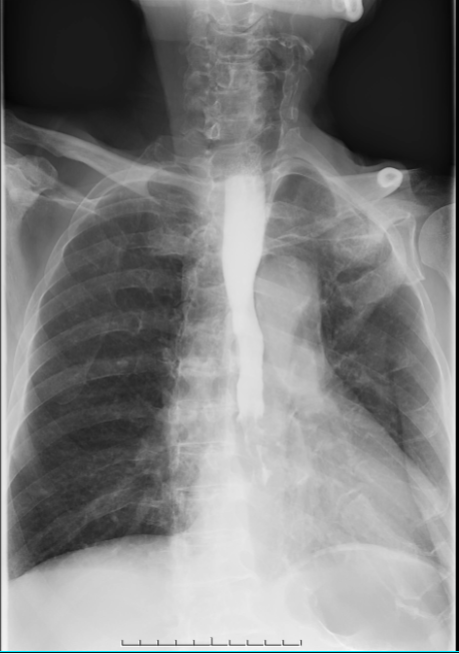

食管造影:患者食管中下段局限性狭窄

面对患者复杂的病情,李建新主持召开多学科联合会诊(MDT)。经与会专家讨论,大家达成共识,认为切除巨脾后有利于经胸腹联合切口显露贲门胃底,解决脾亢所致的血小板减少,于是决定先行手术,解除食管梗阻,术中输注血小板,加强抗感染,积极防治出血,改善情况后,恢复营养摄入,为后续白血病及食管癌的化疗创造条件。